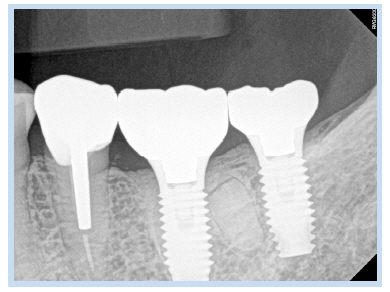

69세 여자 환자가 하악 좌측 제1, 2대구치 상실로 인한 저작의 어려움을 주소로 내원하였다. 하악 좌측 제1, 2대 구치는 6년 전 발치된 상태였고, 하악 좌측 제1대구치의 치근이 잔존해 있는 상태였다(Fig. 1). 내원하기 1개월 전 하악 좌측 제1대구치 부위에 통증이 있었다고 하였지만, 내원 시에는 통증이 없는 상태였다. 심장센터에서 부정맥 치료 중인 환자로 하악 좌측 제1대구치 잔존 치근을 발거하고 하악 좌측 제1, 2대구치 부위에 임플란트를 식립하기로 계획하였다. #46 잔존 치근을 발거하고 치조정 절개를 가하여 피판을 거상한 후 임플란트 drilling을 시행하였다. 그 후 하악 제1대구치에 직경 4.8 mm, 길이 1.5 mm의 임플란트, 하악 제2대구치에 직경 4.8 mm, 길이 10 mm의 임플란트를 일회법으로 식립(Osstem SS II; Osstem Implant, Seoul, Korea)하였다. 치유 지대주(healing abutment)를 연결 후 피판을 재위치시키고 4-0 Vicryl (Johnson & Johnson, New Brunswick, NJ, USA)로 봉합하였다. 임플란트 식립 1주일 후 봉합사를 제거하고 파노라마 방사선 사진과 치근단 방사선 사진을 촬영하였다. 이때 #36 부위에 원심 치근으로 추정되는 방사선 불투과상이 관찰되었으나 감염 등 특별한 증상이 없었고 잔존 치근을 무리하게 제거한다면 그로 인한 골소실 및 임플란트 골유착에 오히려 방해가 될 수 있다고 판단하여 잔존시킨 상태에서 정기적 관찰을 결정하였다(Fig. 2, 3). 임플란트 식립 2개월 후 최종 보철물이 장착되었으며 임플란트 식립 후 115개월간의 치근단 방사선 사진을 통한 경과 관찰 시 안정적으로 임플란트가 유지되고 있음을 관찰할 수 있었다(Fig. 4, 5).

Fig. 5. Periapical radiograph 115 months after implant placement. Distinct Radiolucency is not observed. Implants show sound condition and do not observe any pathological findings.